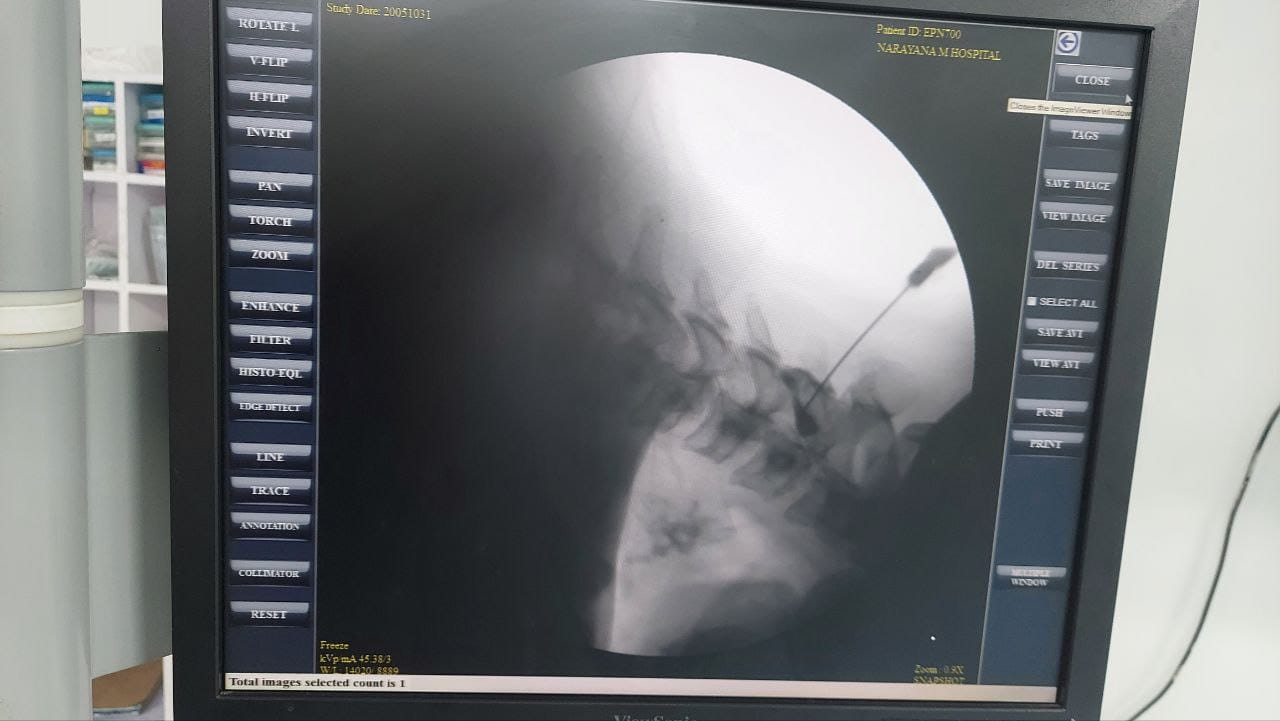

Procedures

Struggling with chronic pain? Get advanced, personalised pain management from Dr. Manish De, one of Kolkata’s leading pain specialists. From knee pain, heel pain, low back pain, frozen shoulder, migraines, cancer pain to post-TKR persistent pain—Dr. De offers safe, evidence-based treatments across multiple locations: